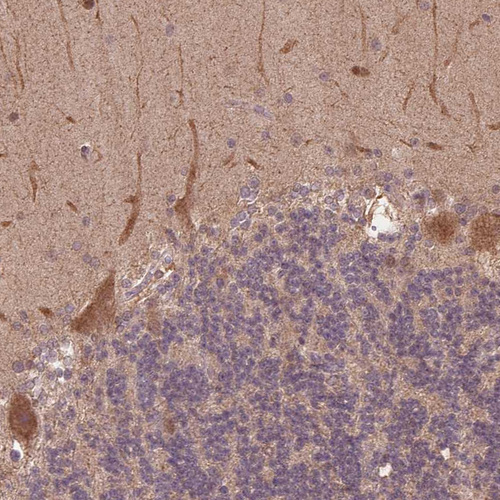

Immunohistochemical staining of human cerebellum shows strong cytoplasmic positivity in Purkinje cells.